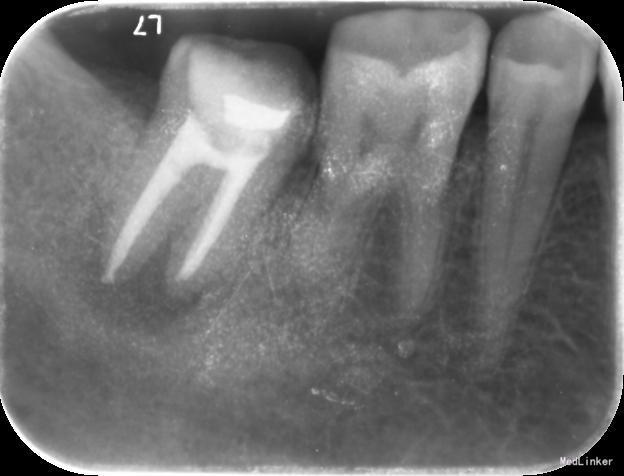

检查:右下7髓腔开放,可见髓腔内食物残渣及部分银汞充填体,叩痛(++), 冷热刺激无反应,松动1度,牙体已制备,牙合龈距离低,X线片示根尖区密度减低区。

诊断:难治性根尖周炎 治疗计划:告知患者病情,治疗难度及预后,拟行根管再治疗,但术后效果不确定,如若不理想拟需行根尖手术甚至牙拔除术。患者知情同意,并要求尽量行保留牙齿治疗。 处置:第一次 揭全髓顶,去腐,疏通根管,测量工作长度,机扩预备至S1,超声荡洗,激光消毒,封CP球。口服抗炎药。一周后复诊。 第二次 复诊无叩痛,暂封物在。去除暂封物,双氧水和盐水交替冲洗,EDTA伴随下根管预备至F2,超声荡洗,激光荡洗+激光消毒,封氢氧化钙。两周后复诊。 第三次 复诊无叩痛,暂封物在。 去除暂封物,双氧水和盐水交替冲洗,EDTA伴随下根管预备至40号,超声荡洗,激光荡洗+激光消毒,封vitapex,玻璃离子体充填。拍X线片。一月后复诊。 第四次 复诊无疼痛 旧充填体在 拍X线片可见根尖阴影变小,故未行任何治疗,嘱患者1月后再次复诊。 第五次 复诊无疼痛 旧充填体在 拍X线片未见根尖阴影变小,故去除旧充填体,冲洗,去除vitpex,根管再次预备,双氧水和盐水交替冲洗,超声荡洗,激光荡洗+激光消毒,封氢氧化钙。两周后复诊。 第六次 复诊无疼痛 去除暂封物,冲洗,见根管内无渗出,试尖,超声荡洗,激光荡洗和消毒,干燥,AHplus糊剂和热牙胶充填,糊剂超填,玻璃离子体充填。请口腔外科医生会诊是否可行根尖手术,外科医生建议因手术难度大,且病变与下颌神经管接近,建议随诊观察,暂不考虑行根尖手术。必要时考虑意向性牙再植术或者牙拔除术。嘱患者1月后复诊,结果患者失诊。